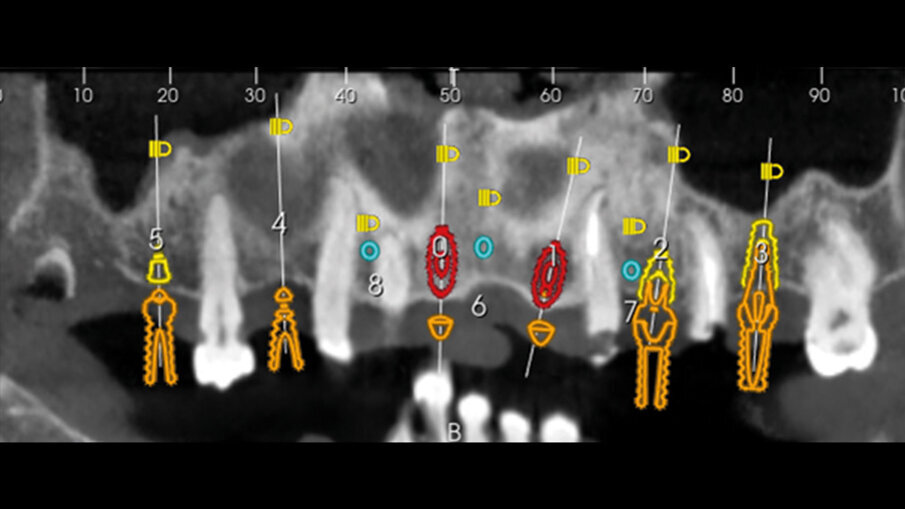

La pianificazione ha previsto innanzitutto l’allineamento all’interno del software dei file DICOM e dei file STL provenienti dalla scansione intraorale (Fig. 5). Il posizionamento degli impianti è stato ragionato in funzione di una ceratura diagnostica preventivamente realizzata con un CAD esterno e importata nel software di chirurgia guidata. Per la riabilitazione dell’arcata superiore, sono stati selezionati 6 impianti intercalati tra i siti post-estrattivi: 3,5 x 13 in posizione 11 e 22, 4 x 13 in posizione 24, 4 x 8 in posizione 26, 4 x 11,5 in posizione 14 e 4 x 10 in posizione 16. Utilizzando le informazioni dei modelli importati (master e ceratura) è stato possibile scegliere preventivamente anche le componenti protesiche in funzione delle emergenze rispetto alla ceratura e allo spessore dei tessuti (Figg. 6-8).